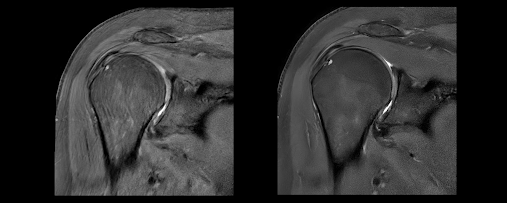

AIR Recon DL has been launched to produce high quality images in a shorter time span. Developed by GE HealthCare, the elevation of the signal to noise ratio helped to cut the exam timing by up to 50%, enabling efficiency from higher quality images. Its development fostered a better approach for radiologists to quickly and effectively perform diagnostic procedures. Health professionals have proven their empowerment from utilizing the AIR Recon DL. For example, according to GE HealthCare, Dr. Pascal Roux, a radiologist, claimed that cases were more convenient to diagnose and they were capable of helping more patients in a shorter time frame. This proves that the AIR Recon development has enabled a healthy environment, inspiring doctors to perform successful procedures for their patients.